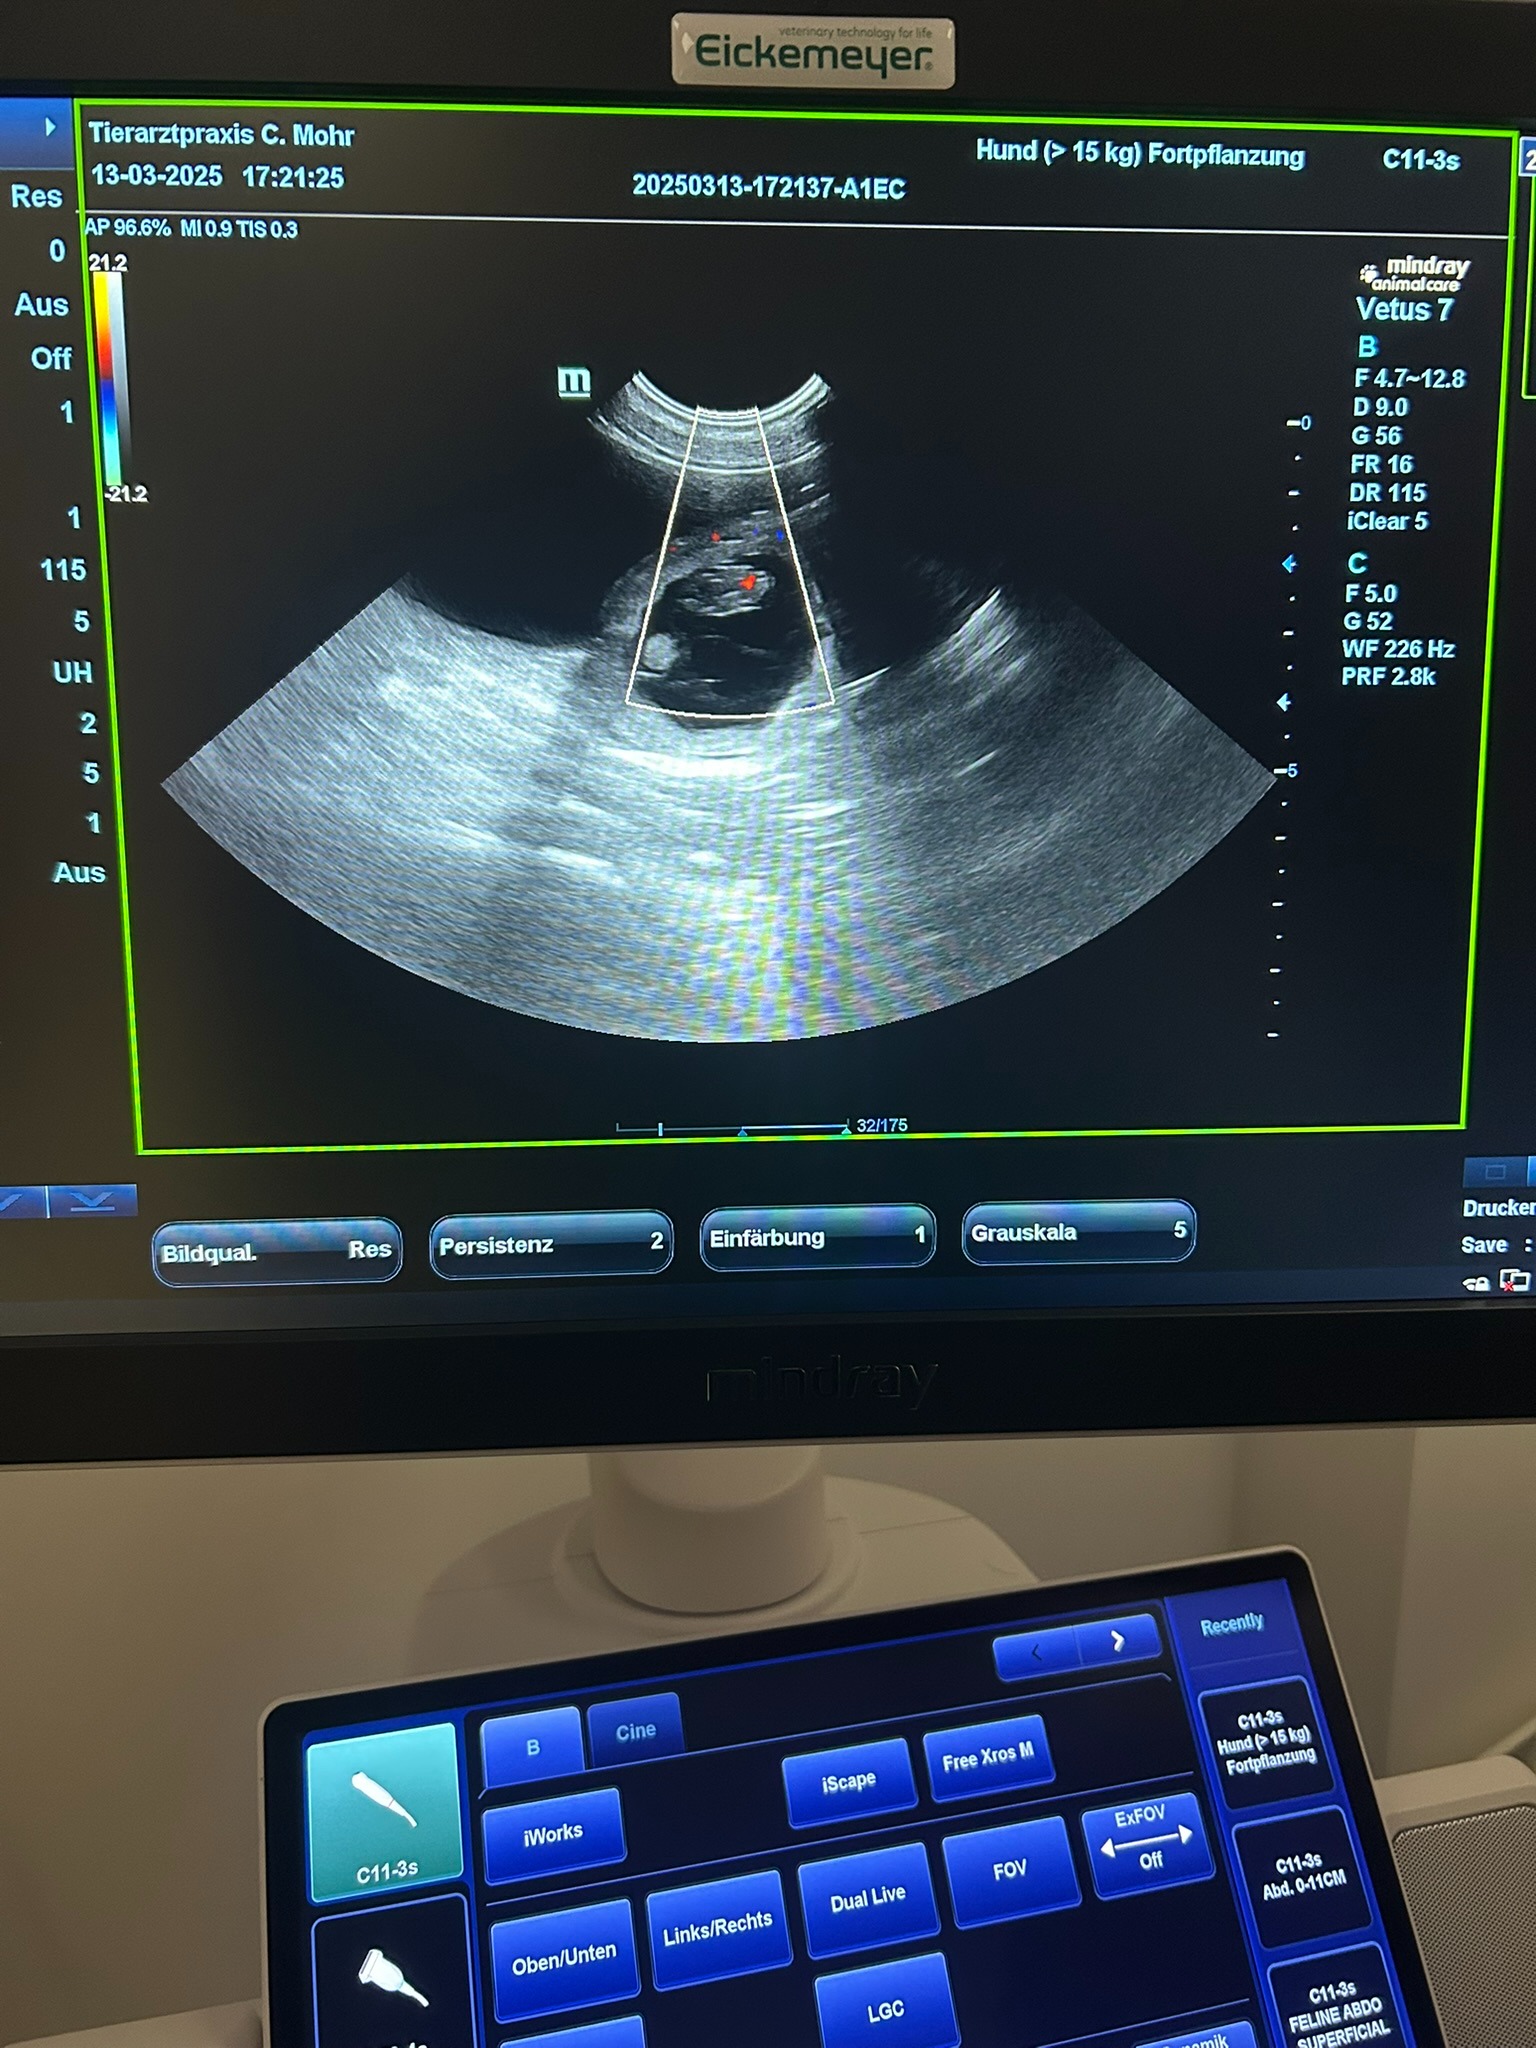

Alma ist trächtig!

3/13/2025

Heute waren wir mit Alma beim Tierarzt. Die Bilder im Ultraschall zeigen mehrere kleine Welpen. Wir freuen uns riesig und erwarten in der Osterwoche Almas Nachwuchs.